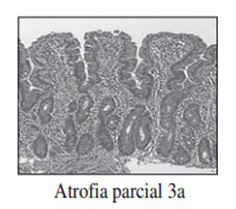

Realizamos una endoscopia digestiva alta y una colonoscopia a la paciente con toma de biopsias, obteniendo el informe de Anatomía patológica.